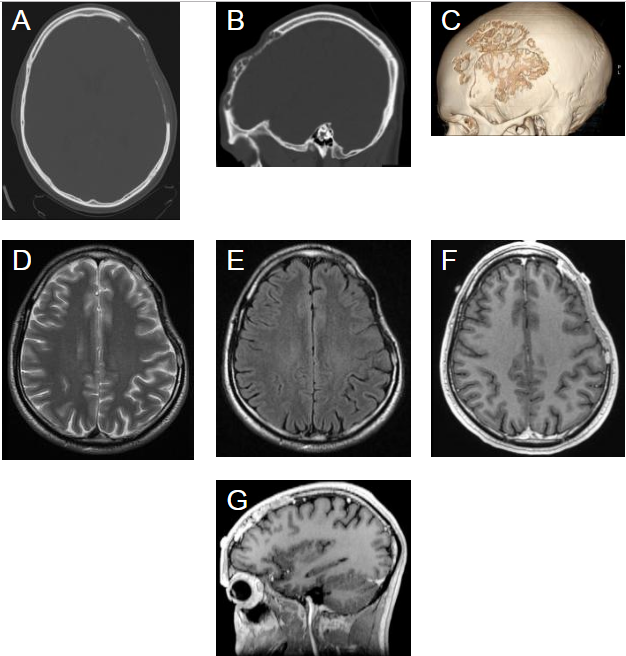

CT骨算法轴向扫描(A),矢状(B)和3D重建(C)提示明确的的骨溶解区域,其中骨中央部分变薄消失,无新骨形成。轴向T2加权(D)和FLAIR(E)序列提示骨中央呈低信号,缺损边缘呈高信号(箭头)。轴向和矢状(G)造影后MPRAGE图像显示沿颅骨缺损区域增强,特别是沿其边缘(箭头)。